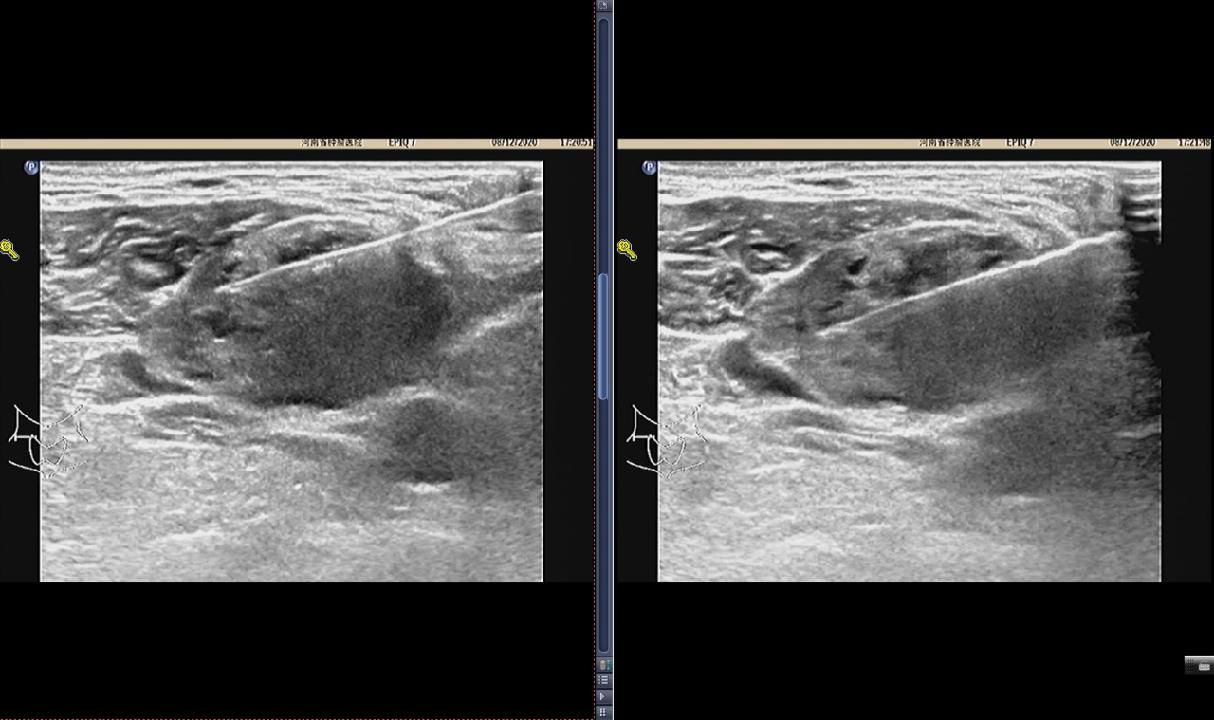

一、超声检查评估原发灶及颈部淋巴结

超声引导下细针穿刺活检(US-FNAB)